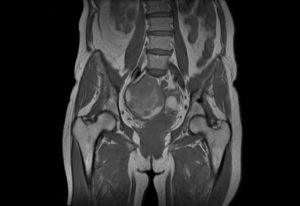

В женском малом тазу расположены внутренние половые органы (матка с придатками, шейка, влагалище), мочевой пузырь и прямая кишка, в мужском — мочевой пузырь, семенные железы, предстательная железа и прямая кишка. Учитывая, что в малом тазу у мужчин и женщин расположены разные органы, показания к назначению МРТ у них также отличаются.

Мрт у мужчин

Органы малого таза мужчины

Мужчине назначают магнитно-резонансное обследование при таких заболеваниях: